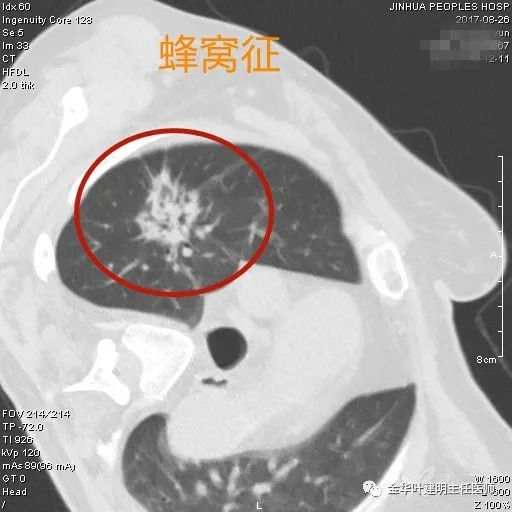

蜂窝征

蜂窝征:病灶多为实性密度或偏实性密度,但其内部有很多小空泡样,以致整体看就像蜂窝。这种病灶初期认识不够,会以为是炎症,其实现在看来,基本都是恶性的,大概是从磨玻璃病灶逐渐变实增密到实性的过程之中,有些区域还不密时,看上去像蜂窝。